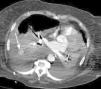

Mujer de 75 años, exfumadora, que ingresa en UCI por insuficiencia respiratoria secundaria a Neumonía. Presenta evolución tórpida, con desarrollo de Síndrome de Distrés Respiratorio Agudo y necesidad de ventilación mecánica prolongada. El destete se ve dificultado por la aparición de derrame pleural (DP) bilateral, por lo que se coloca un drenaje pleural ecoguiado (Pleurocath® 12 French). A los 30 minutos presenta cuadro de hipotensión severa, sudoración y palidez. Tras estabilización inicial se solicita TAC torácico, que objetiva hemotórax derecho y una imagen redondeada que sugiere pseudoaneurisma de circulación pulmonar periférica (fig. 1). Se contacta con Radiología Intervencionista y se decide realizar angiografía pulmonar, confirmando la existencia de un pseudoaneurisma arterial procedente de una rama de la lobar descendente derecha (fig. 2). Se emboliza con coils (fig. 3), presentando buena evolución y siendo dada de alta a planta sin incidencias.